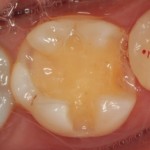

シーラント処置前

-

シーラント処置後